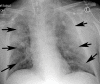

The coronavirus disease 2019 (COVID-19) pandemic is a global health care emergency. Although reverse-transcription polymerase chain reaction testing is the reference standard method to identify patients with COVID-19 infection, chest radiography and CT play a vital role in the detection and management of these patients. Prediction models for COVID-19 imaging are rapidly being developed to support medical decision making. However, inadequate availability of a diverse annotated data set has limited the performance and generalizability of existing models. To address this unmet need, the RSNA and Society of Thoracic Radiology collaborated to develop the RSNA International COVID-19 Open Radiology Database (RICORD). This database is the first multi-institutional, multinational, expert-annotated COVID-19 imaging data set. It is made freely available to the machine learning community as a research and educational resource for COVID-19 chest imaging. Pixel-level volumetric segmentation with clinical annotations was performed by thoracic radiology subspecialists for all COVID-19-positive thoracic CT scans. The labeling schema was coordinated with other international consensus panels and COVID-19 data annotation efforts, the European Society of Medical Imaging Informatics, the American College of Radiology, and the American Association of Physicists in Medicine. Study-level COVID-19 classification labels for chest radiographs were annotated by three radiologists, with majority vote adjudication by board-certified radiologists. RICORD consists of 240 thoracic CT scans and 1000 chest radiographs contributed from four international sites. It is anticipated that RICORD will ideally lead to prediction models that can demonstrate sustained performance across populations and health care systems.